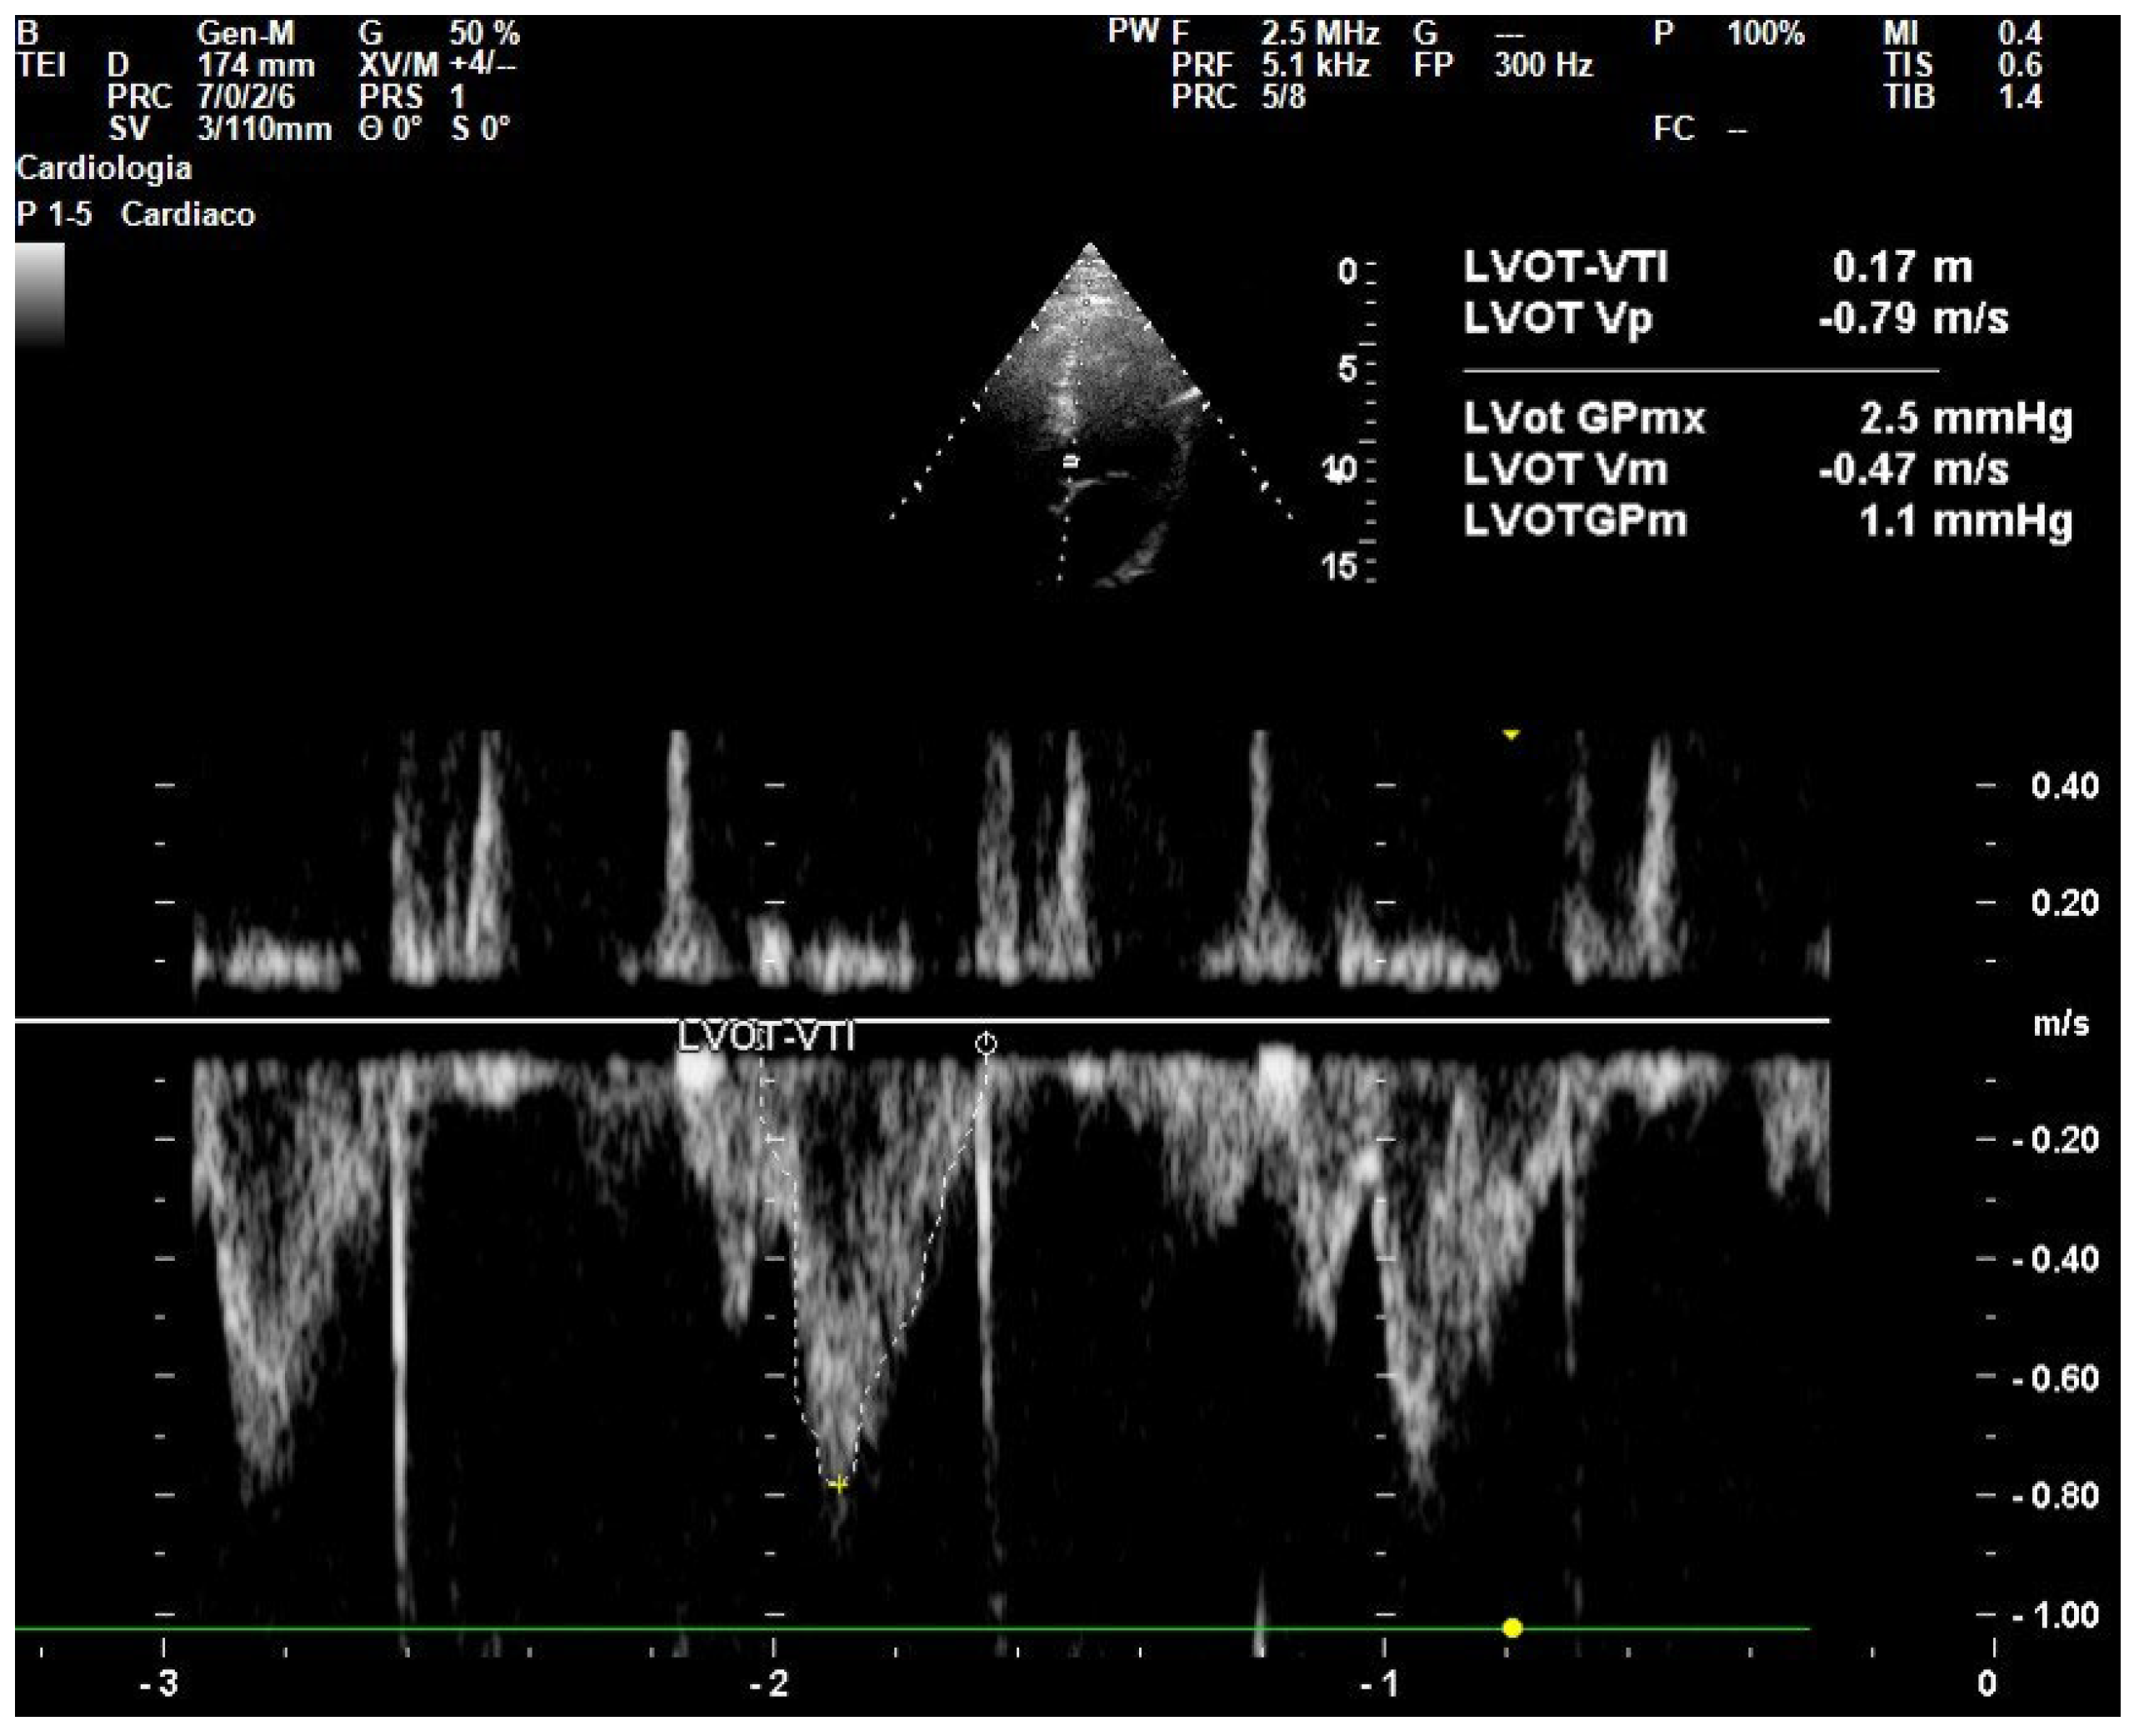

| LVOT | Left Ventricular Outflow Tract |

- Wang, J.; Zhou, D.; Gao, Y.; Wu, Z.; Wang, X.; Lv, C. Effect of VTILVOT Variation Rate on the Assessment of Fluid Responsiveness in Septic Shock Patients. Medicine 2020, 99, e22702. [Google Scholar] [CrossRef]

- Dinh, V.A.; Ko, H.S.; Rao, R.; Bansal, R.C.; Smith, D.D.; Kim, T.E.; Nguyen, H.B. Measuring Cardiac Index with a Focused Cardiac Ultrasound Examination in the ED. Am. J. Emerg. Med. 2012, 30, 1845–1851. [Google Scholar] [CrossRef]

- Chanthawatthanarak, S.; Boonasa, K.; Apiratwarakul, K.; Cheung, L.W.; Tiamkao, S.; Ienghong, K. Agreement between Carotid and LVOT Non-Invasive Cardiac Output Measurements in ED Septic Shock Patients: A Prospective Observational Study. Sci. Rep. 2025, 15, 19911. [Google Scholar] [CrossRef]

- Parker, C.W.; Kolimas, A.M.; Kotini-Shah, P. Velocity-Time Integral: A Bedside Echocardiography Technique Finding a Place in the Emergency Department. J. Emerg. Med. 2022, 63, 382–388. [Google Scholar] [CrossRef]